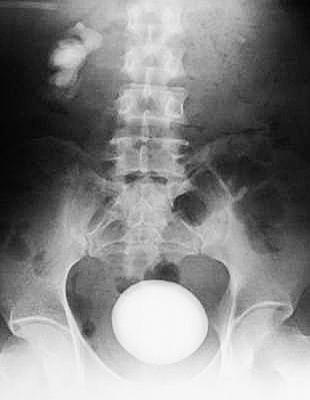

结石如“一轮明月”占满整个膀胱。

花生米大小的结石15年间竟然长成鹅蛋大,像“一轮明月”挂在小伙子的膀胱处。昨天,31岁的河南安阳付先生在武汉京都结石病医院,成功无创取出罕见膀胱巨石。

在建筑工地工作的付先生,患膀胱结石已有15年,因久拖不治结石长到直径10余厘米。从CT片上看,结石如“一轮明月”占满整个膀胱(如图)。不愿意接受开放式取石手术,他连夜赶到武汉京都结石病医院求助无创取石。